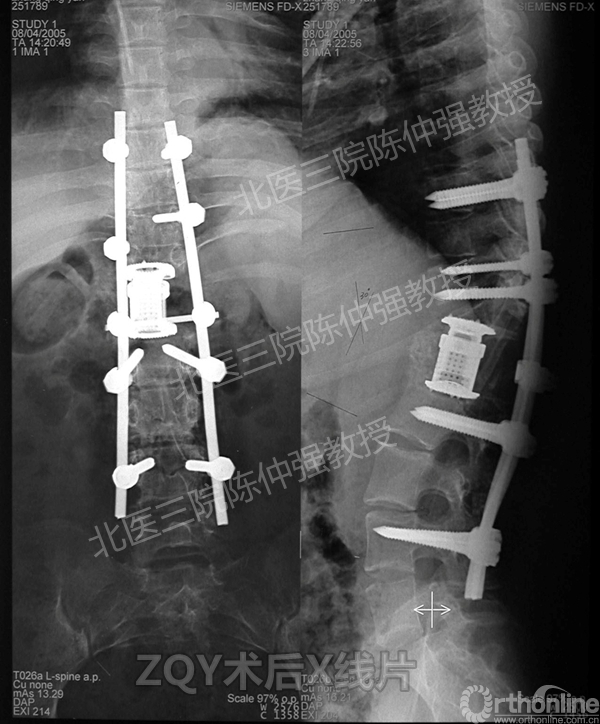

ZQY术后

患者女性17岁,胸腰椎陈旧结核性侧后凸畸形,局部呈“麻花状”扭转,无神经功能受损表现。2005年,陈仲强教授带领团队实施后路+侧前方联合入路脊柱节段切除、双轴旋转矫形术。术后患者外观显著改善,神经功能正常。术后随访证实患者截骨矫形节段骨性融合良好,矫形效果持续良好。